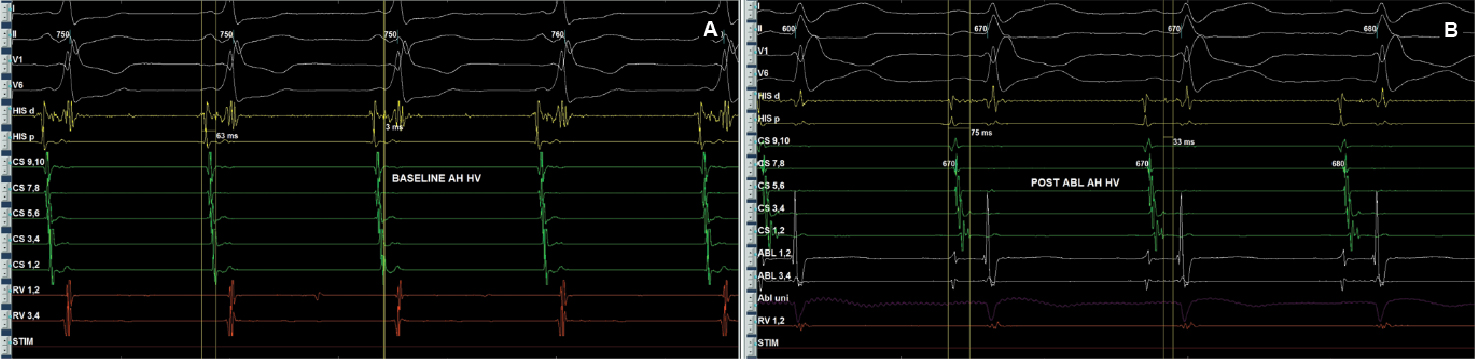

After written informed consent, patient was taken for electrophysiological study. Two quadripolar diagnostic catheters were advanced under fluoroscopy to His bundle region and right ventricular apex. One decapolar catheter was advanced into the coronary sinus. During the electrophysiological study at baseline, atrial-His bundle (AH) and His-ventricular (HV) intervals were 85 ms and 3 ms in sinus rhythm, respectively. There were no atrioventricular (AV) conduction abnormalities. A narrow complex tachycardia (tachycardia cycle length [TCL] = 400 ms) was easily induced during catheter placement with following features: initiation of the tachycardia with a critical AH interval, fixed 1:1 ventriculoatrial (VA) conduction, concentric retrograde activation with VA interval of 37 ms, a post-pacing interval (PPI, 576 ms)–TCL (406 ms) >115 (170 ms) and ventricular overdrive pacing resulted in a VAHV response. His synchronized and early premature ventricular contraction (PVC) did not reset the tachycardia. His synchronized premature atrial contraction (PAC) also failed to reset the tachycardia. The tachycardia was reproducible and consistent (Fig. 2). After confirming the diagnosis of typical AV nodal re-entrant tachycardia (AVNRT) a decision was taken for slow pathway ablation. Using a steerable ablation catheter, with the help of intracardiac electrograms (EGMs) and using fluoroscopy, the region of the slow pathway was identified. Radiofrequency applications were made in the region of the slow pathway while constantly monitoring temperature, impedance, ECG and intracardiac EGMs, monitoring for fast junctional conduction and radiofrequency energy was halted if there was evidence of VA block. Radiofrequency ablation resulted in a junctional rhythm with intact AV conduction, which is a typical response. The AV nodal slow pathway was successfully modified (Fig. 3).

Figure 6. Intracardiac intervals baseline (A) showed HV interval of 3 ms that was normalized (B) after successful accessory pathway ablation.